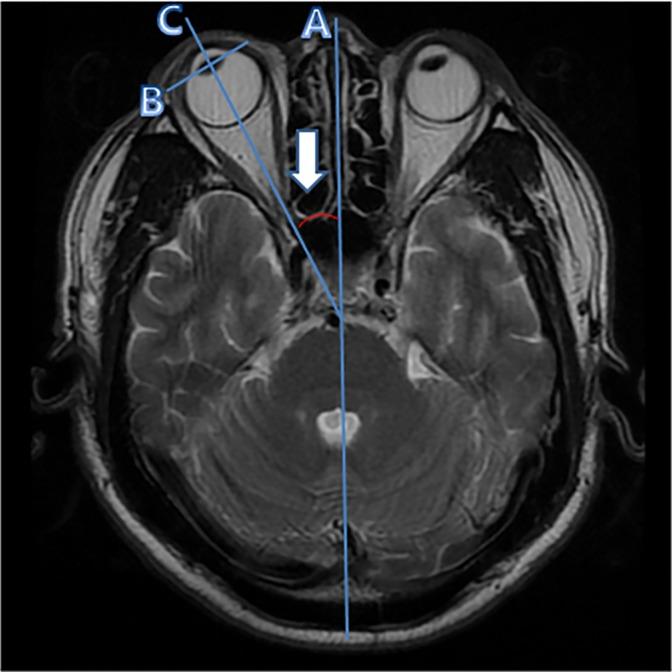

In our previous study, we found that horizontal ocular deviation (OD) was significantly increased in patients with unilateral vestibular neuritis (VN). This study is aimed to compare the measurements of horizontal OD in various diseases which can present as acute vertigo in the emergency department. We retrospectively reviewed patients who visited the emergency department and underwent brain MRI due to acute vertigo. We compared them to healthy controls who underwent brain MRI for a regular health examination. Among the study participants, 149 patients who were diagnosed with benign paroxysmal positional vertigo (BPPV), unilateral Ménière's disease (MD), vestibular migraine (VM), unilateral vestibular neuritis (VN), or posterior inferior cerebellar artery (PICA) infarction were enrolled. Absolute angles of horizontal OD were larger in the definite MD (19.1 ± 12.7°), possible and probable MD (15.5 ± 11.7°), and VN (22.2 ± 11.7°) groups compared to the control group (4.3 ± 3.7°). Most VN patients (83.3%) had horizontal OD toward the direction of the lesion. About half of the MD patients (46.2%) and half of the patients with PICA infarction (50.0%) had horizontal OD toward the opposite direction of the lesion. Regarding PICA infarction, horizontal OD was observed only in patients who immediately underwent an MRI after developing the PICA territory vestibulocerebellar infarction. Although the exact mechanism of horizontal OD is unclear, this study suggests that horizontal OD reflects a static vestibular imbalance, and that the eyeball is deviated to the weaker of the two vestibular nuclei during neural resting activity. Therefore, horizontal OD could be helpful in assessing for a prior vestibular imbalance.

在我们之前的研究中,我们发现单侧前庭神经炎(VN)患者的水平眼球偏斜(OD)显著增加。本研究旨在比较各种疾病中水平 OD 的测量值,这些疾病在急诊科可表现为急性眩晕。我们回顾性分析了因急性眩晕而到急诊科就诊并接受脑部 MRI 检查的患者,并将其与因常规健康检查而接受脑部 MRI 检查的健康对照者进行比较。在研究参与者中,纳入了 149 名被诊断为良性阵发性位置性眩晕(BPPV)、单侧梅尼埃病(MD)、前庭性偏头痛(VM)、单侧前庭神经炎(VN)或后下小脑动脉(PICA)梗死的患者。与对照组(4.3±3.7°)相比,明确 MD(19.1±12.7°)、可能 MD 和可能 MD(15.5±11.7°)和 VN(22.2±11.7°)组的水平 OD 绝对角度更大。大多数 VN 患者(83.3%)的水平 OD 朝向病变侧。约一半的 MD 患者(46.2%)和一半的 PICA 梗死患者(50.0%)的水平 OD 朝向病变对侧。关于 PICA 梗死,仅在发生 PICA 区域前庭小脑梗死后立即进行 MRI 的患者中观察到水平 OD。虽然水平 OD 的确切机制尚不清楚,但本研究表明,水平 OD 反映了一种静态前庭不平衡,在神经静息活动期间,眼球偏向较弱的两个前庭核之一。因此,水平 OD 可能有助于评估先前的前庭不平衡。